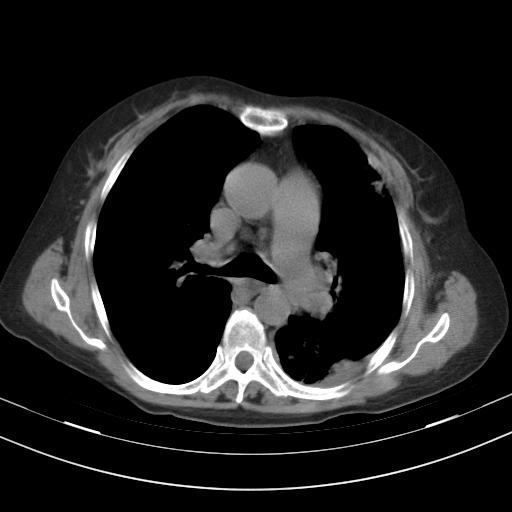

老年女性,嗜睡3天,意识模糊。轻咳,无发热。

两肺慢支炎伴感染,左侧胸腔积液。纵膈及双侧肺门淋巴结肿大建议复查。

1)两肺感染性病变;建议抗炎治疗后复查。2)纵隔淋巴结肿大。3)左侧胸腔积液。